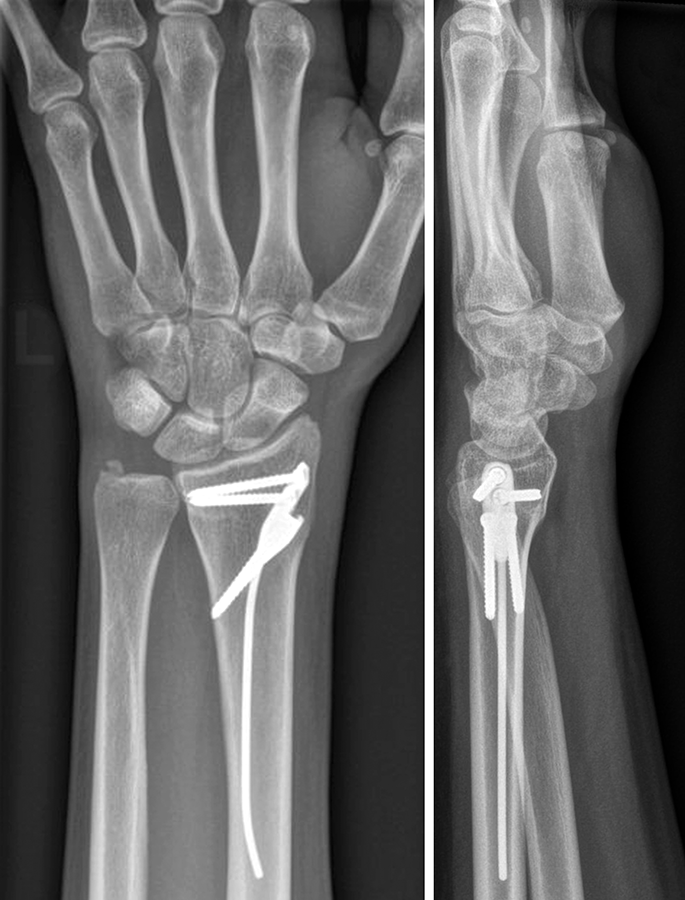

The patient was a 25-year-old woman who sustained a displaced, unstable extraarticular fracture of the left distal radius while snowboarding.

After closed reduction a dorsal re-dislocation of 25° occurred (Fig 3a). There are additional apparent signs of instability: dorsal comminution (Fig 3a) and fracture of the ulnar styloid (Fig 3b). Therefore, a considerable potential for further dislocation is present which is likely to occur in a cast. This young, active, and demanding patient wishes to return to her activities as early as possible. This can only be achieved with an operative fracture fixation. The nail was chosen instead of a plate. This allowed an almost instant functional use of her hand, which allowed her to return to work at 2 weeks postoperatively without additional fixation or a splint and full unprotected function of her wrist at 6 weeks.